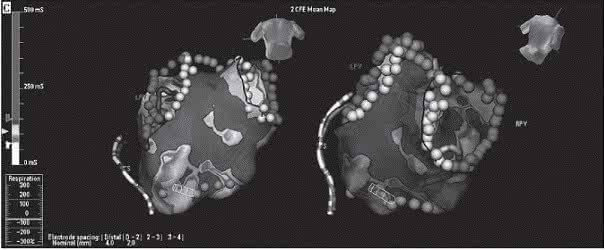

1、药物和非药物方法既无法转复,药物又无法控制快速(大于100次/分)心率的房颤。这样的房颤病人其心率始终是快的,用射频消融 的方法去打断房室结,阻断快速的心房冲动下传心室,使心室率不 再受快速的心房率控制和影响,用起搏器发放电脉冲控制心室跳动频 率(心率),频率应答起搏器可根据病人的实际需要随时变更发放的 频率次数,即近似正常的心率。

2、心率时快时慢的房颤。这样的房颤 病人其心率一会儿快一会儿慢,用药控制快速心率,心率能变得很慢 (小于40次/分),以致造成危险危及病人生命安全。用药改善缓慢 的心率,心率可能变得很快(大于100次/分),以致病人无法耐受快 速的心率。用药物抑制快速的心房率,用起搏器维持心率”正常”。